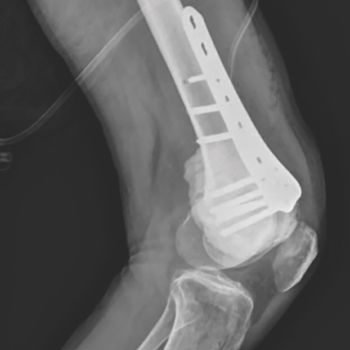

Hans Kristian Nugraha, MD, SpOT, and colleagues detail the potential benefits of an arthroscopic surgical approach through a case study of a patient with giant cell tumor of bone.